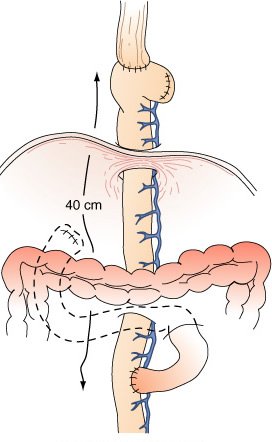

Reconstrução do esôfago distai em Y de Roux após esofagectomia distai e gastrectomia total para tumor comprometendo a cárdia e o estômago